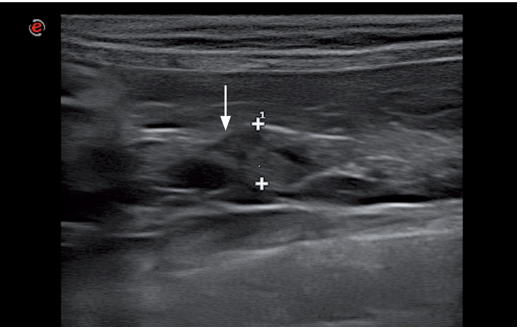

结节增生

经常会在老年猫的胰腺上偶然发现结节性增生。胰腺结节性增生的超声影像表现为多个直径小于1cm的,等回声或低回声,边界清晰的小结节(图18-20)。胰腺结节性增生可能与胰腺增厚具有关。胰腺结节性增生与胰腺肿瘤的形态有些相似,但结节性增生更倾向于呈现为多个较小的结节。结节性增生也容易与囊性病灶相混淆,但它们没有后方回声增强。